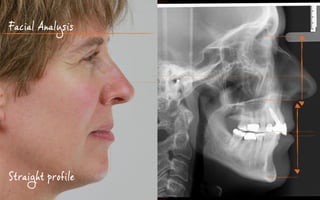

Facial Analysis

Straight profile